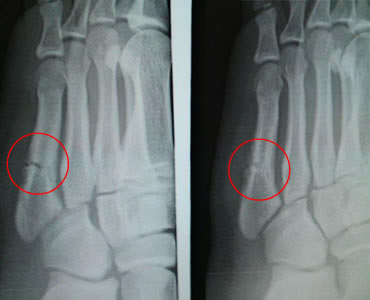

14歳(中学生/バスケットボール選手)男性 症状:中足骨骨折 (酸素カプセル)

おかげさまで、病院でも7~80%は外側の硬い骨も出来ていると言われました。

回復の経過

酸素カプセル利用経過 2月26日 スタート時

酸素カプセル利用経過 3月19日 初期

酸素カプセル利用経過 4月9日 中期

酸素カプセル利用 4月23日 終了